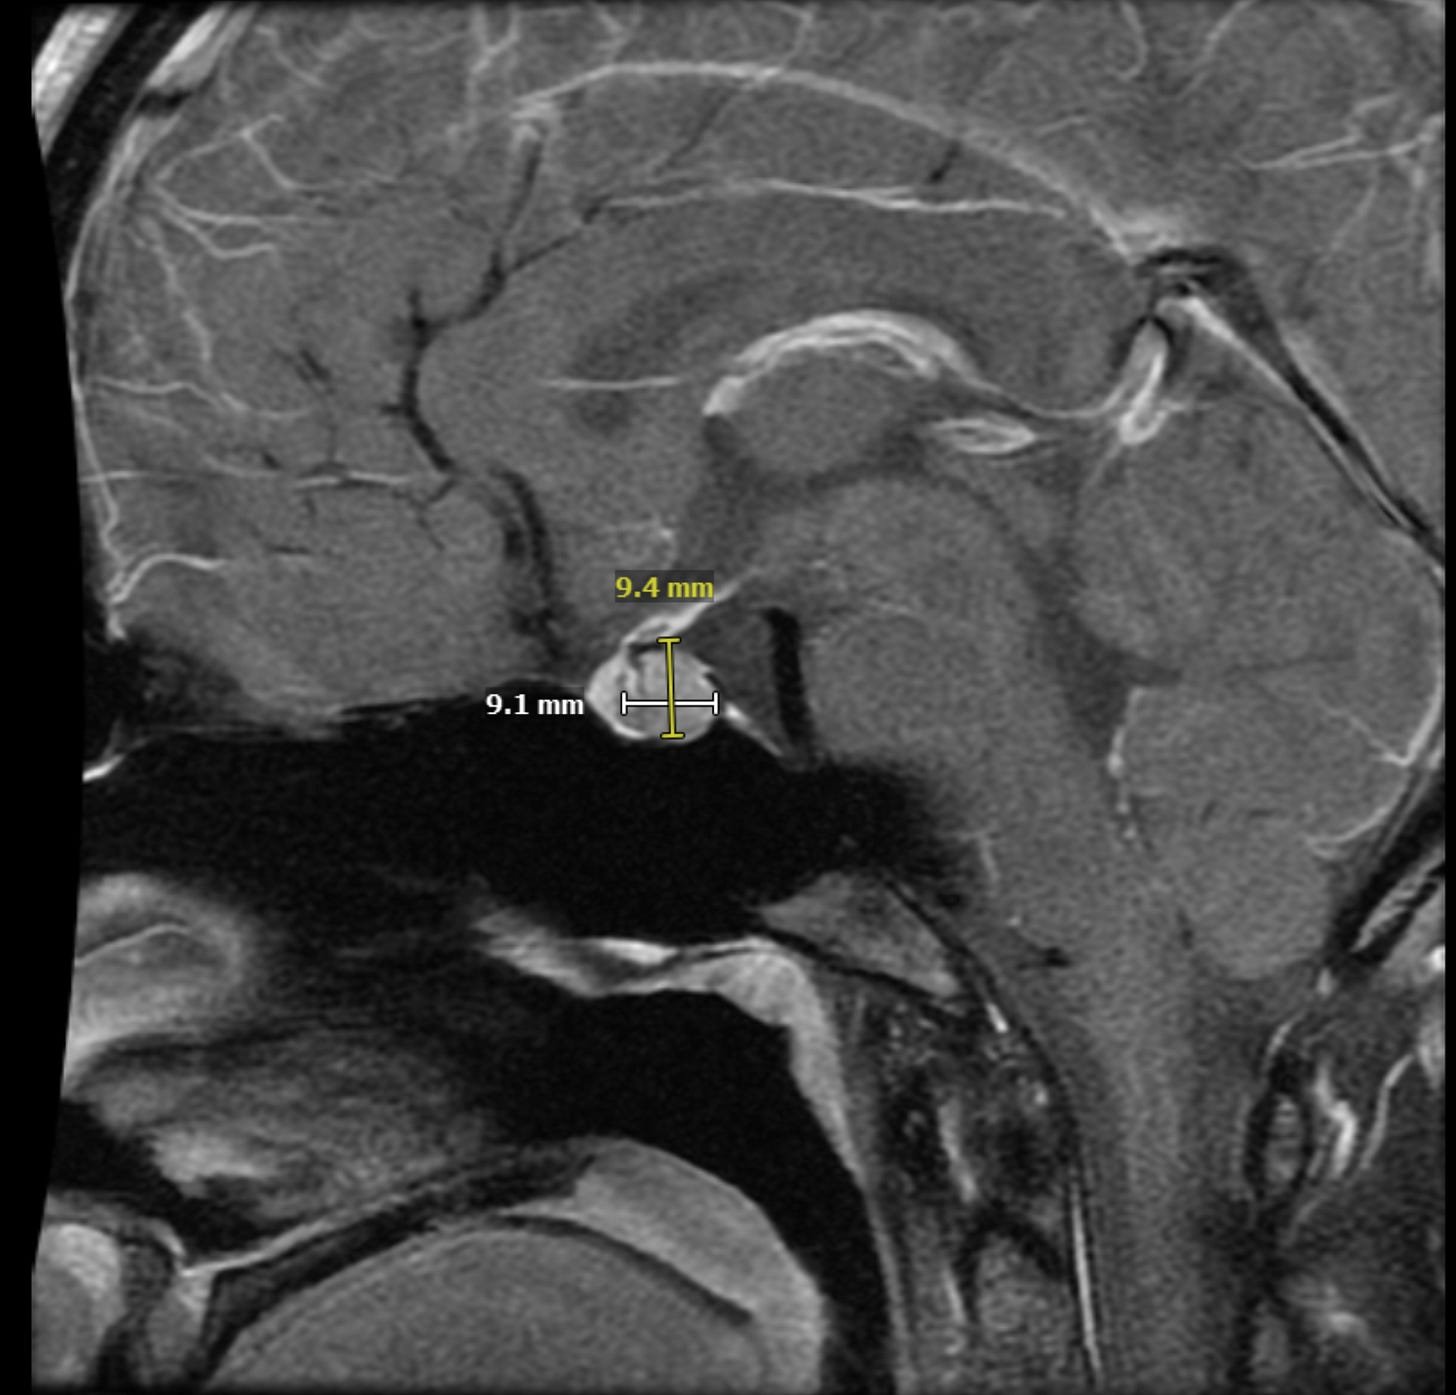

When Andrew Rodriguez noticed subtle changes in his girlfriend Amy's health—fatigue, missed periods, dwindling bone density—doctors dismissed it as stress or burnout. Six months later, an MRI revealed a prolactinoma: a pituitary tumor overproducing prolactin at 16x normal levels. Their journey through two failed surgeries and conflicting expert opinions reveals a harsh truth: even "solved" diseases harbor devastating unknowns. This experience became the catalyst for a radical experiment: Can AI-driven research democratize medical breakthroughs?

First MRI showing Amy's prolactinoma (Credit: Andrew Rodriguez)